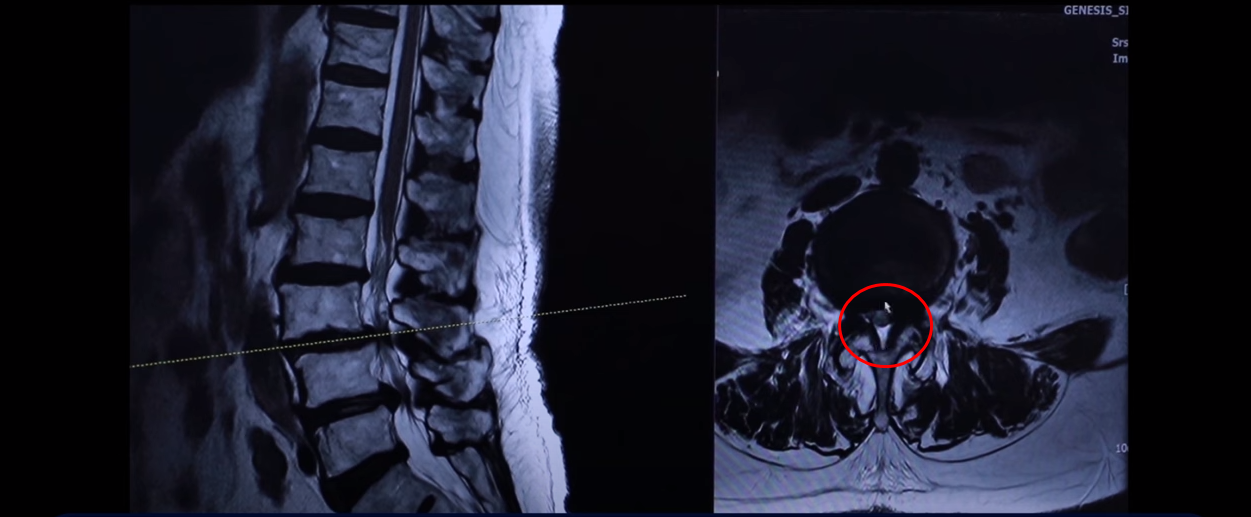

이분 76세 여자 환자분 MRI를 보겠습니다. 이분 MRI를 보시면 보시다시피 허리 여러 마디가 퇴행돼 있고 전방전위가 있습니다. 뼈가 밀려나가 있죠.

그리고 이렇게 뼈가 밀려나간 전방전위증을 가지신 분들은 허리가 오랫동안 아프신 분들이 많습니다. 이분도 한 5년 정도 허리가 아프셨고 그때그때 신경 주사 맞으면서 버티고 사셨는데 신경주사라는 건 맞다 보면 점점 효과가 떨어집니다. 그리고 결국은 다리 증상들이 심하게 생겨서 걷지를 못하게 되시는 거죠. 걷는 거리도 점점 짧아지고 다리는 왜 저리게 되냐면 이분의 이렇게 전방전위증이 있는 마디를 보면 척추관이 좀 좁아져 있지만 아주 많이 좁지 않습니다.

그런데 특히 이 아랫마디 가보면 여기가 많이 좁아져 있습니다. 특히 뭐가 문제냐면 이 척추관보다는 여기 추간공을 보면 이렇게 좁아져 있습니다. 다른 데하고 굉장히 크게 차이가 많이 나죠.

이제 이렇게 환자들이 이런 걸 보시면 아예 까맣게 변해 있다. 신경이 많이 눌리니까 이게 왼쪽 다리로 가는 신경입니다. 그 다음에 오른쪽 다리로 가는 신경을 보면 신경이 여기 지금 까맣게 보입니다. 이 지방이 다 없어져버린 겁니다. 신경 공간이 좁아져 있죠.

그 다음에 이거는 디스크고 이 뒤에 있는 건 황색인대입니다. 이것들이 지금 두꺼워져 있기 때문에 여기 공간이 좁아지는 겁니다. 그래서 이제 오른쪽 다리, 왼쪽 다리가 다 신경이 눌리고 아파서 못 걷는 분입니다.

이분 근육 상태를 이 MRI에서 볼 수 있는 부분이 있습니다. 특히 이 하부 요추 5번 1번에서 보시면 이게 허리를 펴주는 기립근이라는 근육입니다.

이 근육을 보시면 왼쪽 화면에 정상적인 기립근의 모양을 비교 해보시면 이런 데가 정상적인 근육은 까맣게 보여야 됩니다. 그게 정상적인 근육인데 보시면 하얗게 변해 있죠. 이게 지방으로 변해버린 겁니다.

이렇게 지방으로 변해버리면 힘을 못 씁니다. 그래서 허리를 펴기도 어렵고 허리를 지탱하기도 어려운 거죠.